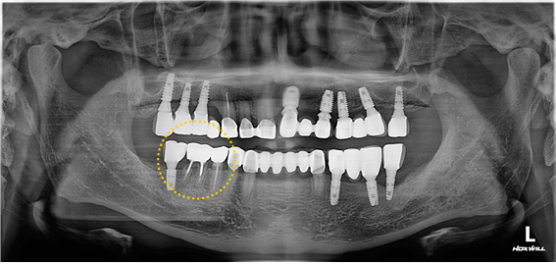

수술 후, 3개월뒤 사진입니다.

이식한 뼈는 완전히 자리를 잡았습니다.

아직은 완벽한 뼈는 아니지만 ISQ # 45 : 80, # 46 : 80 으로

골유착은 완벽히 이루어진걸 확인 후 본을 뜨고 보철물을 완성합니다.